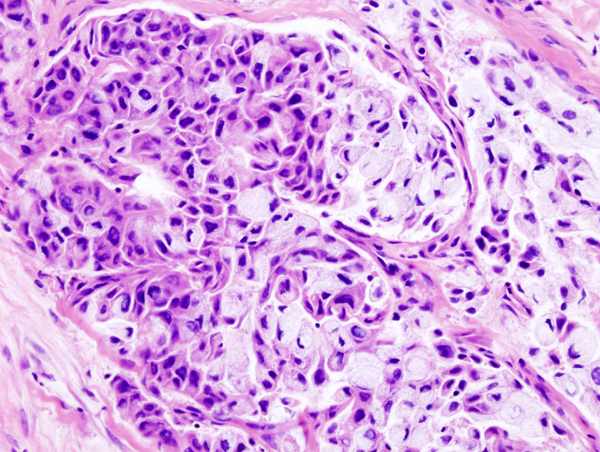

Mucoepidermoid Carcinoma

Mucoepidermoid carcinoma is a malignant tumor made up of squamous and mucin-producing cells.

Mucoepidermoid carcinoma is the most common malignant tumor of the salivary gland.

Mucoepidermoid carcinoma often occurs in the parotid.

The facial nerve is frequently compromised by mucoepidermoid carcinoma.